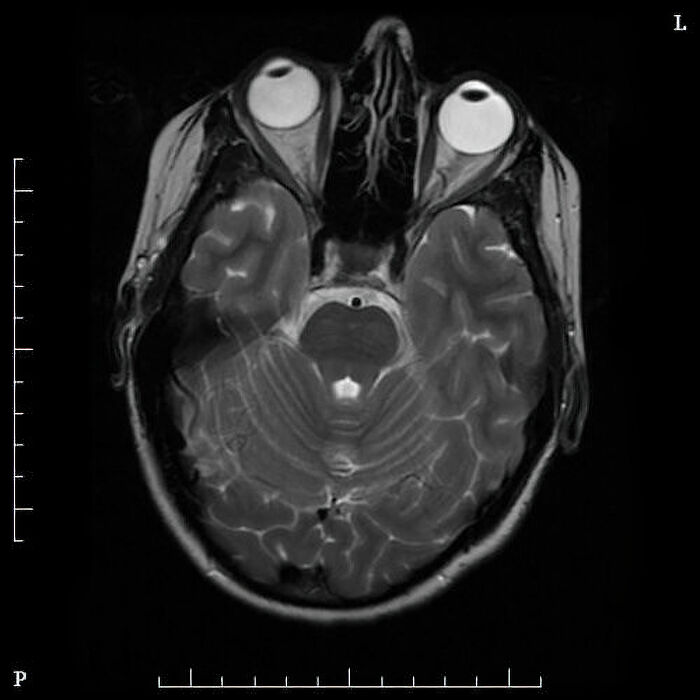

#50

Sitis Inversus is a rare medical condition where your internal organs are entirely mirrored. It presents no issues whatsoever until trying to diagnose something. For example, the telltale sign of appendicitis is pain in the lower right. Someone with sitis Inversus will have their appendix in the lower right, which is usually how it’s discovered.